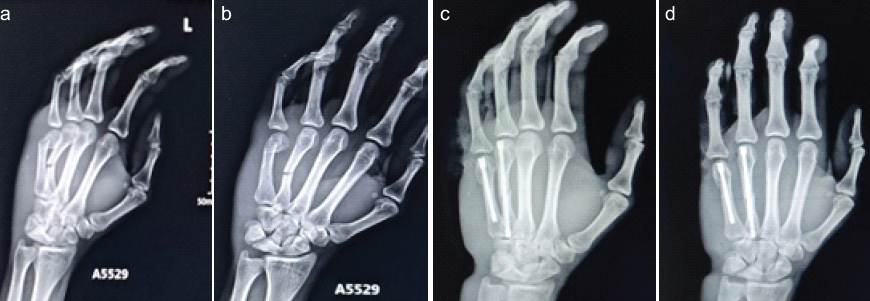

Patient in supine, with affected limb in arm table, parts painted and draped. A skin incision of size 1 cm was made over the dorsal aspect of MCP joint. Extensor tendons incised longitudinally with proximal phalanx in maximal flexion to expose the metacarpal head. After closed reduction of the fracture, a guide wire was inserted from the metacarpal head and passed across the fracture site. With fracture in reduction, medullary canal reaming is done with a cannulated drill bit. Appropriate size Herbert screw inserted and tightened – interfragmentary compression achieved (Fig. 3a, b, c, d). Head of the screw must be buried under the metacarpal head to prevent joint irritation (Fig. 4a, b, c, d). Wound wash given. Suturing done in layers. Sterile dressing done. Post-operative immobilization was not done. Out of 20 cases, two cases needed percutaneous reduction of fracture.

Figure 3: (a and b) Pre-operative X-ray left hand showing # of 4th, 5th metacarpals, and (c and d) after Herbert screw fixation.

Figure 4: (a and b) Pre-operative X-ray left hand showing # of 4th, 5th metacarpals, and (c and d) after Herbert screw fixation.